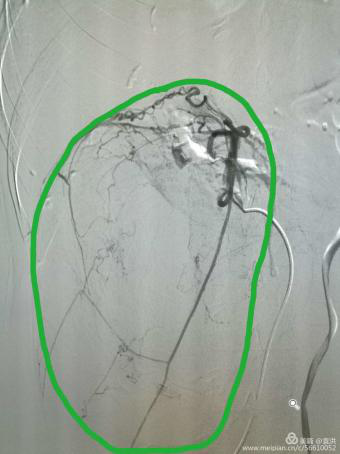

介入治療中“經(jīng)導(dǎo)管栓塞術(shù)”是通過(guò)阻斷血管內(nèi)血流而達(dá)到治療各種類(lèi)型的大出血、血管異常或者為豐富血供的病變預(yù)栓塞,為特大外科手術(shù)創(chuàng)造無(wú)出血的條件。術(shù)前DSA引導(dǎo)下行病變血管栓塞,可有效地減少術(shù)中出血, 使手術(shù)視野更清楚, 腫瘤更易于暴露, 使鄰近的解剖結(jié)構(gòu)更容易顯露, 為順利、徹底切除腫瘤創(chuàng)造了條件。術(shù)中出血少,也有利于患者術(shù)后的恢復(fù)。

(介入DSA下造影提示:腫瘤供血豐富

存在廣泛的側(cè)枝血管供血)